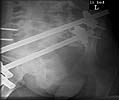

Ankle Xray - Click to Magnify